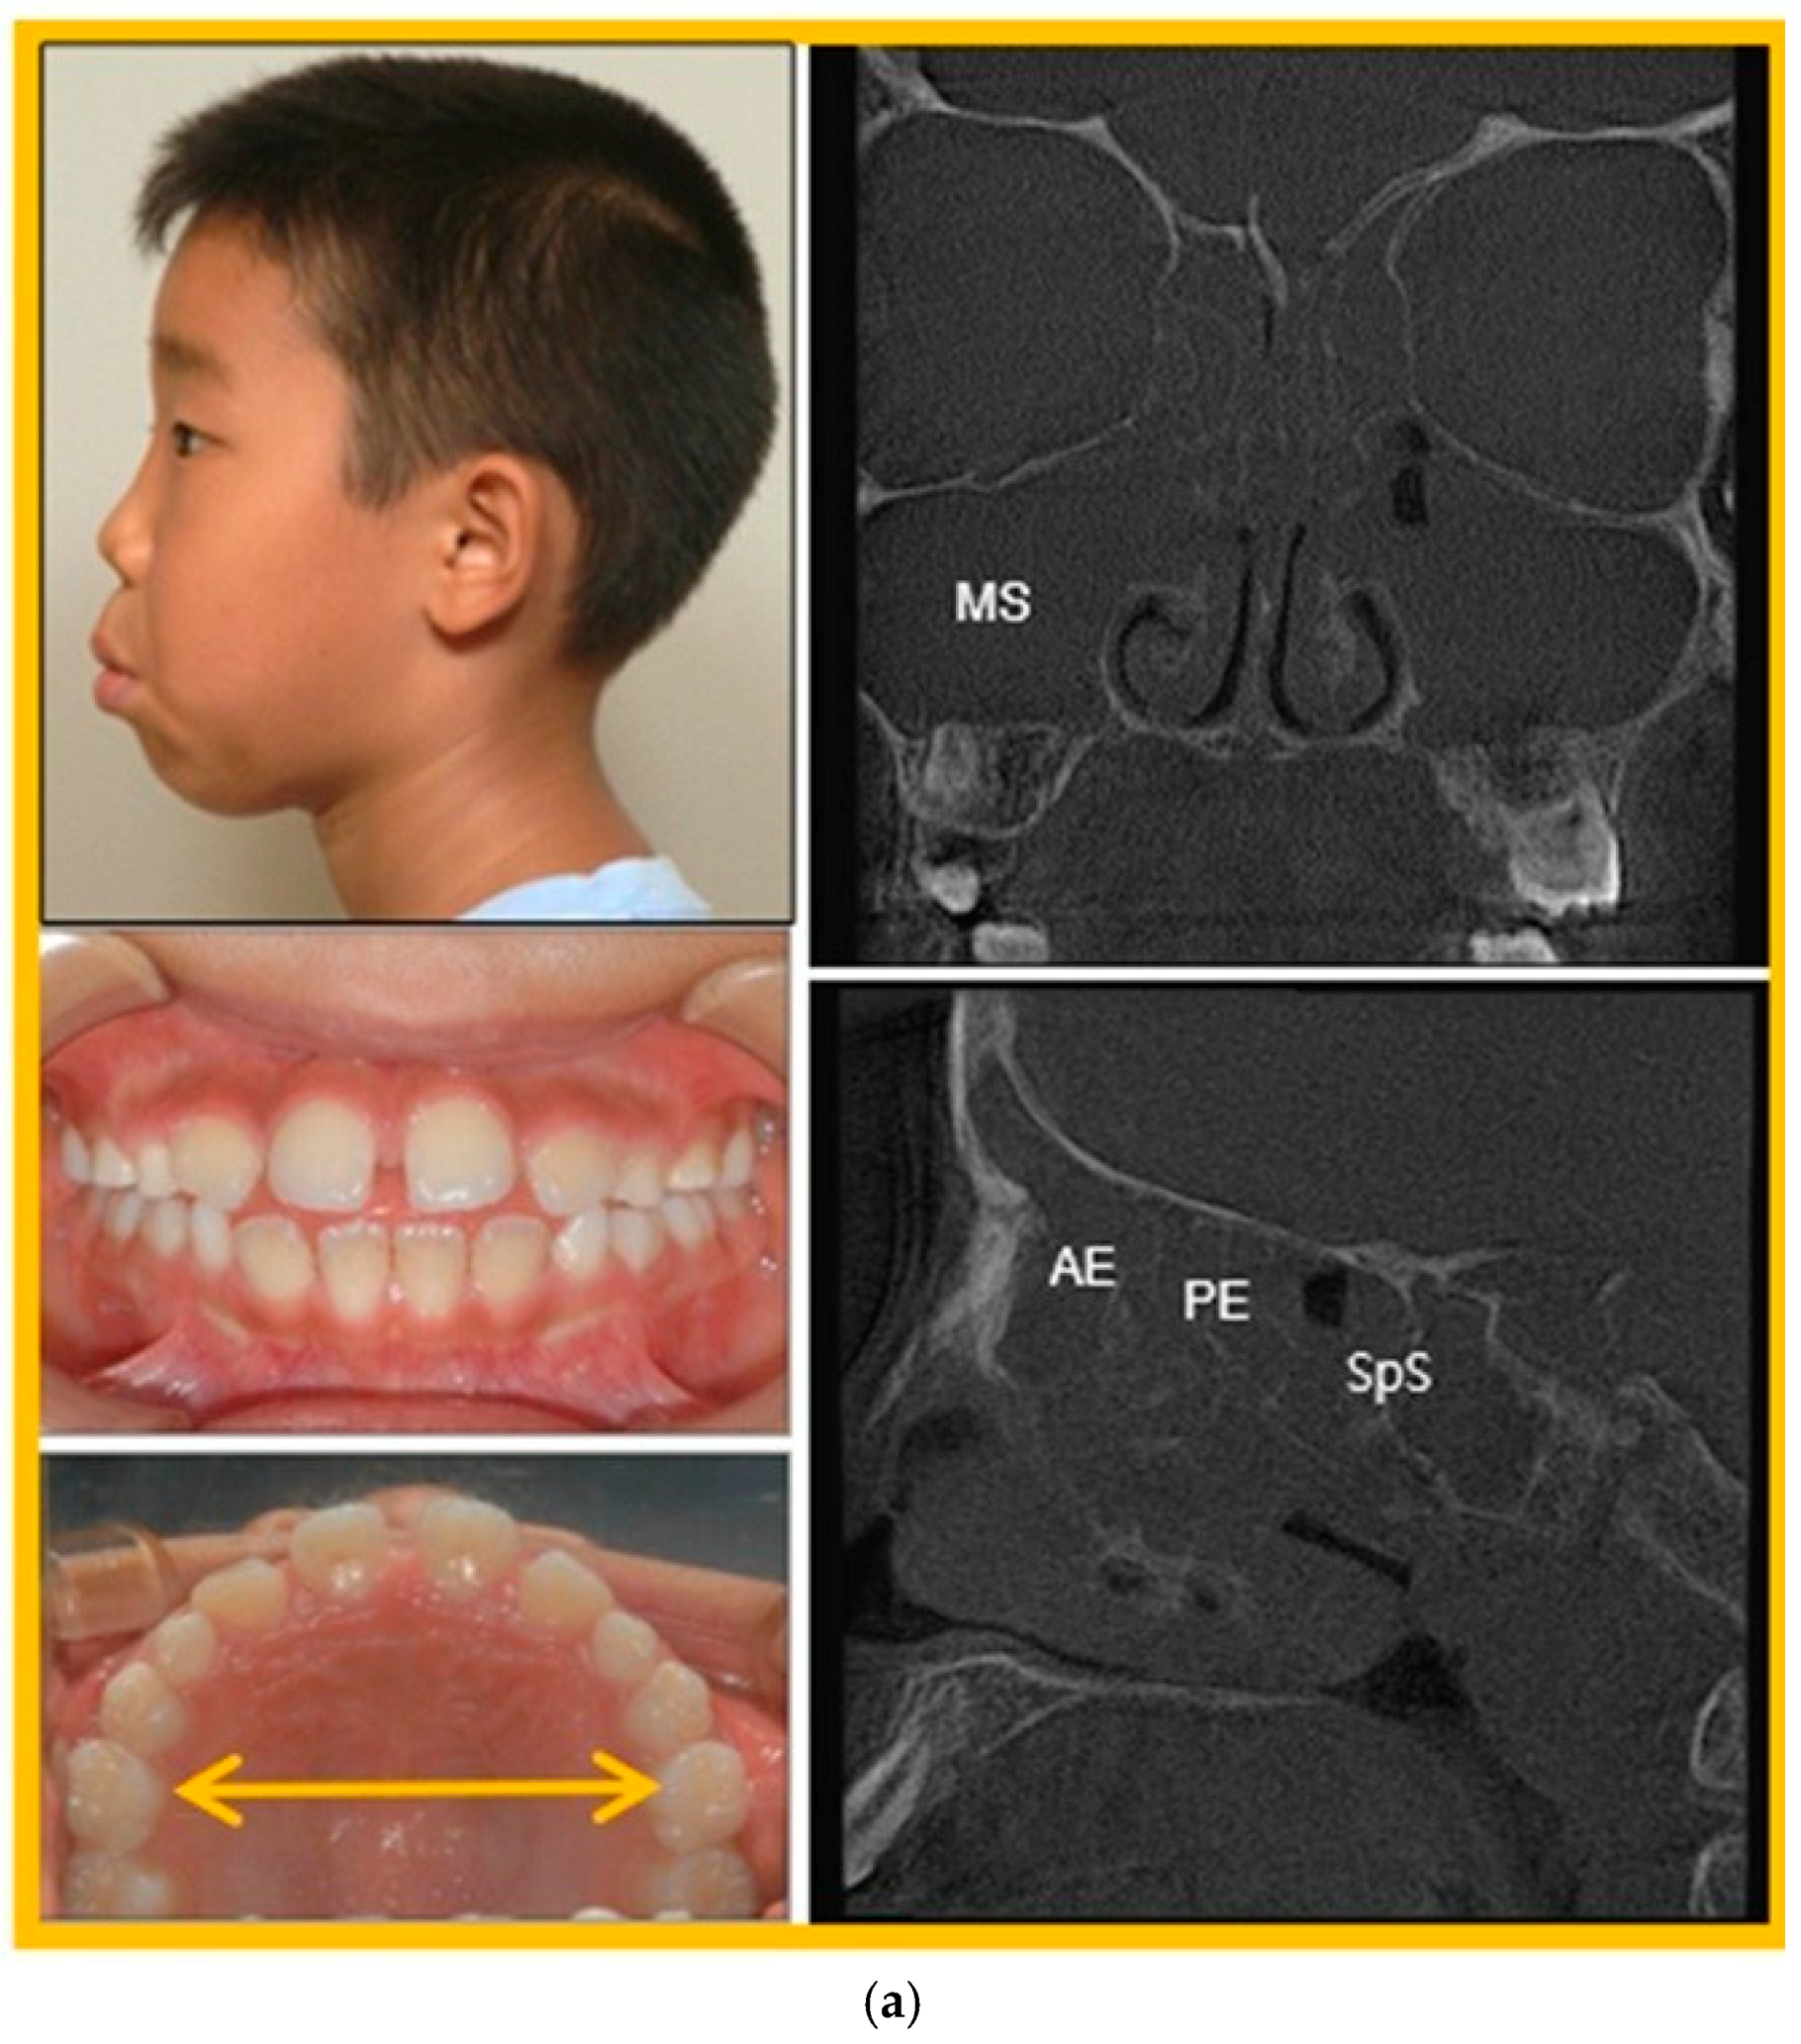

3.3. Patient Case Report